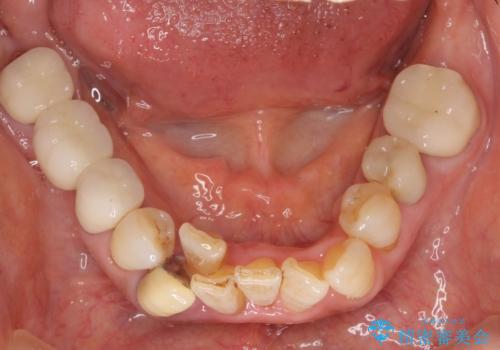

親知らずの移植 4年半経過症例 70代女性

- 親知らずの移植治療から4年半経過した患者様です。

移植した親知らずは全く問題ないそうで、「まるで自分の歯のようです。本当にすごい技術ですね。」とおっしゃって下さいました。

歯肉の腫脹や退縮、動揺も認められませんでした。

4年半前に行った自家歯牙移植に大変ご満足頂き、ご家族も紹介して下さいました。

自家歯牙移植は40歳以上の場合、若年者に比べ成功率が低くなるとの報告もありますが、状態によっては移植が可能な場合もあります。